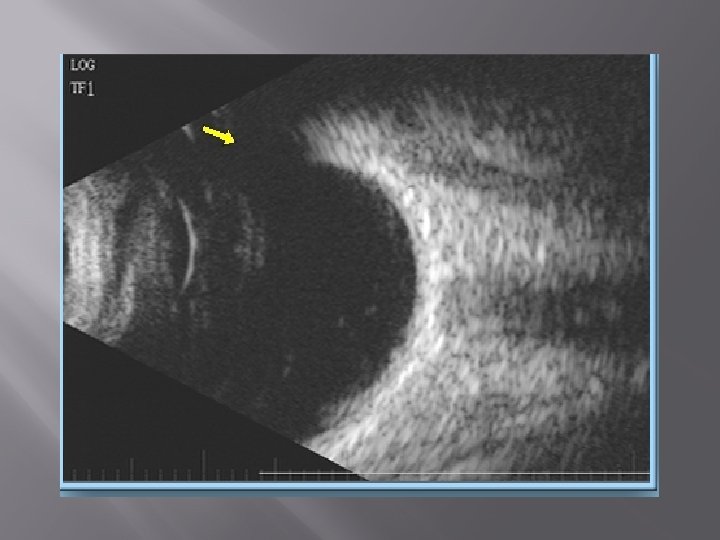

Rhegmatogenous retinal detachment is seen as a uniform V shaped membrane attached to optic disc posteriorly and ora serrata anteriorly. It maintains its echotexture even at low gains. On dynamic B scan it moves with the eyeball and stops as soon as eyeball stops. On A scan it has 80 -100 percent reflectivity.